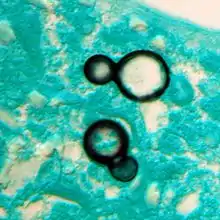

Blastomycosis is caused by dimorphic fungi in the genus Blastomyces, in the phylum Ascomycota and family Ajellomycetaceae. In eastern North America, the most common cause of blastomycosis is Blastomyces dermatitidis, but Blastomyces gilchristii has been associated with some outbreaks. In western North America, many cases of blastomycosis are caused by Blastomyces helicus, which most commonly attacks immunodeficient people and domestic animals. The species Blastomyces percursus causes many cases of blastomycosis in Africa and the Middle East.[14] In Africa, blastomycosis may also be caused by Blastomyces emzantsi, which is often associated with infections outside the lungs.[22]

In endemic areas, Blastomyces dermatitidis lives in soil and rotten wood near lakes and rivers. Although it has never been directly observed growing in nature, it is thought to grow there as a cottony white mold, similar to the growth seen in artificial culture at 25 °C. The moist, acidic soil in the surrounding woodland harbors the fungus.

Once suspected, the diagnosis of blastomycosis can usually be confirmed by demonstration of the characteristic broad based budding organisms in sputum or tissues by KOH prep, cytology, or histology.[27] Tissue biopsy of skin or other organs may be required in order to diagnose extra-pulmonary disease. Blastomycosis is histologically associated with granulomatous nodules.